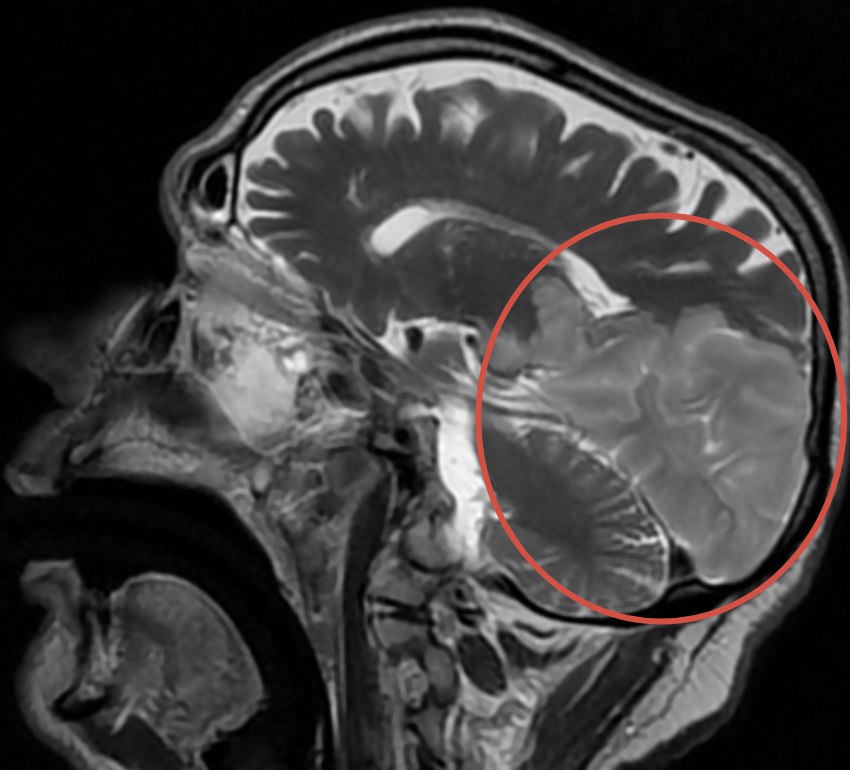

В нашем отделении уже через час была выполнена МРТ головного мозга, и диагноз подтвердился: острое нарушение мозгового кровообращения (инсульт).

В нашем случае МРТ показала инсульт в правой затылочной доле (в бассейне правой задней мозговой артерии).